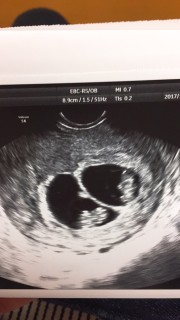

第三子、四子となる二卵性の双子です。 17日前に検診に行った時は胎嚢がふたつしか見えずにいたので今日心拍確認出来てホッとしました。 ふたりとも1センチあるね~と先生が言っていました。人間らしくなっていて感動! まさかの双子ちゃんで慌ててますがこの小さなふたつの命を大事に育てていきたいです(^^)